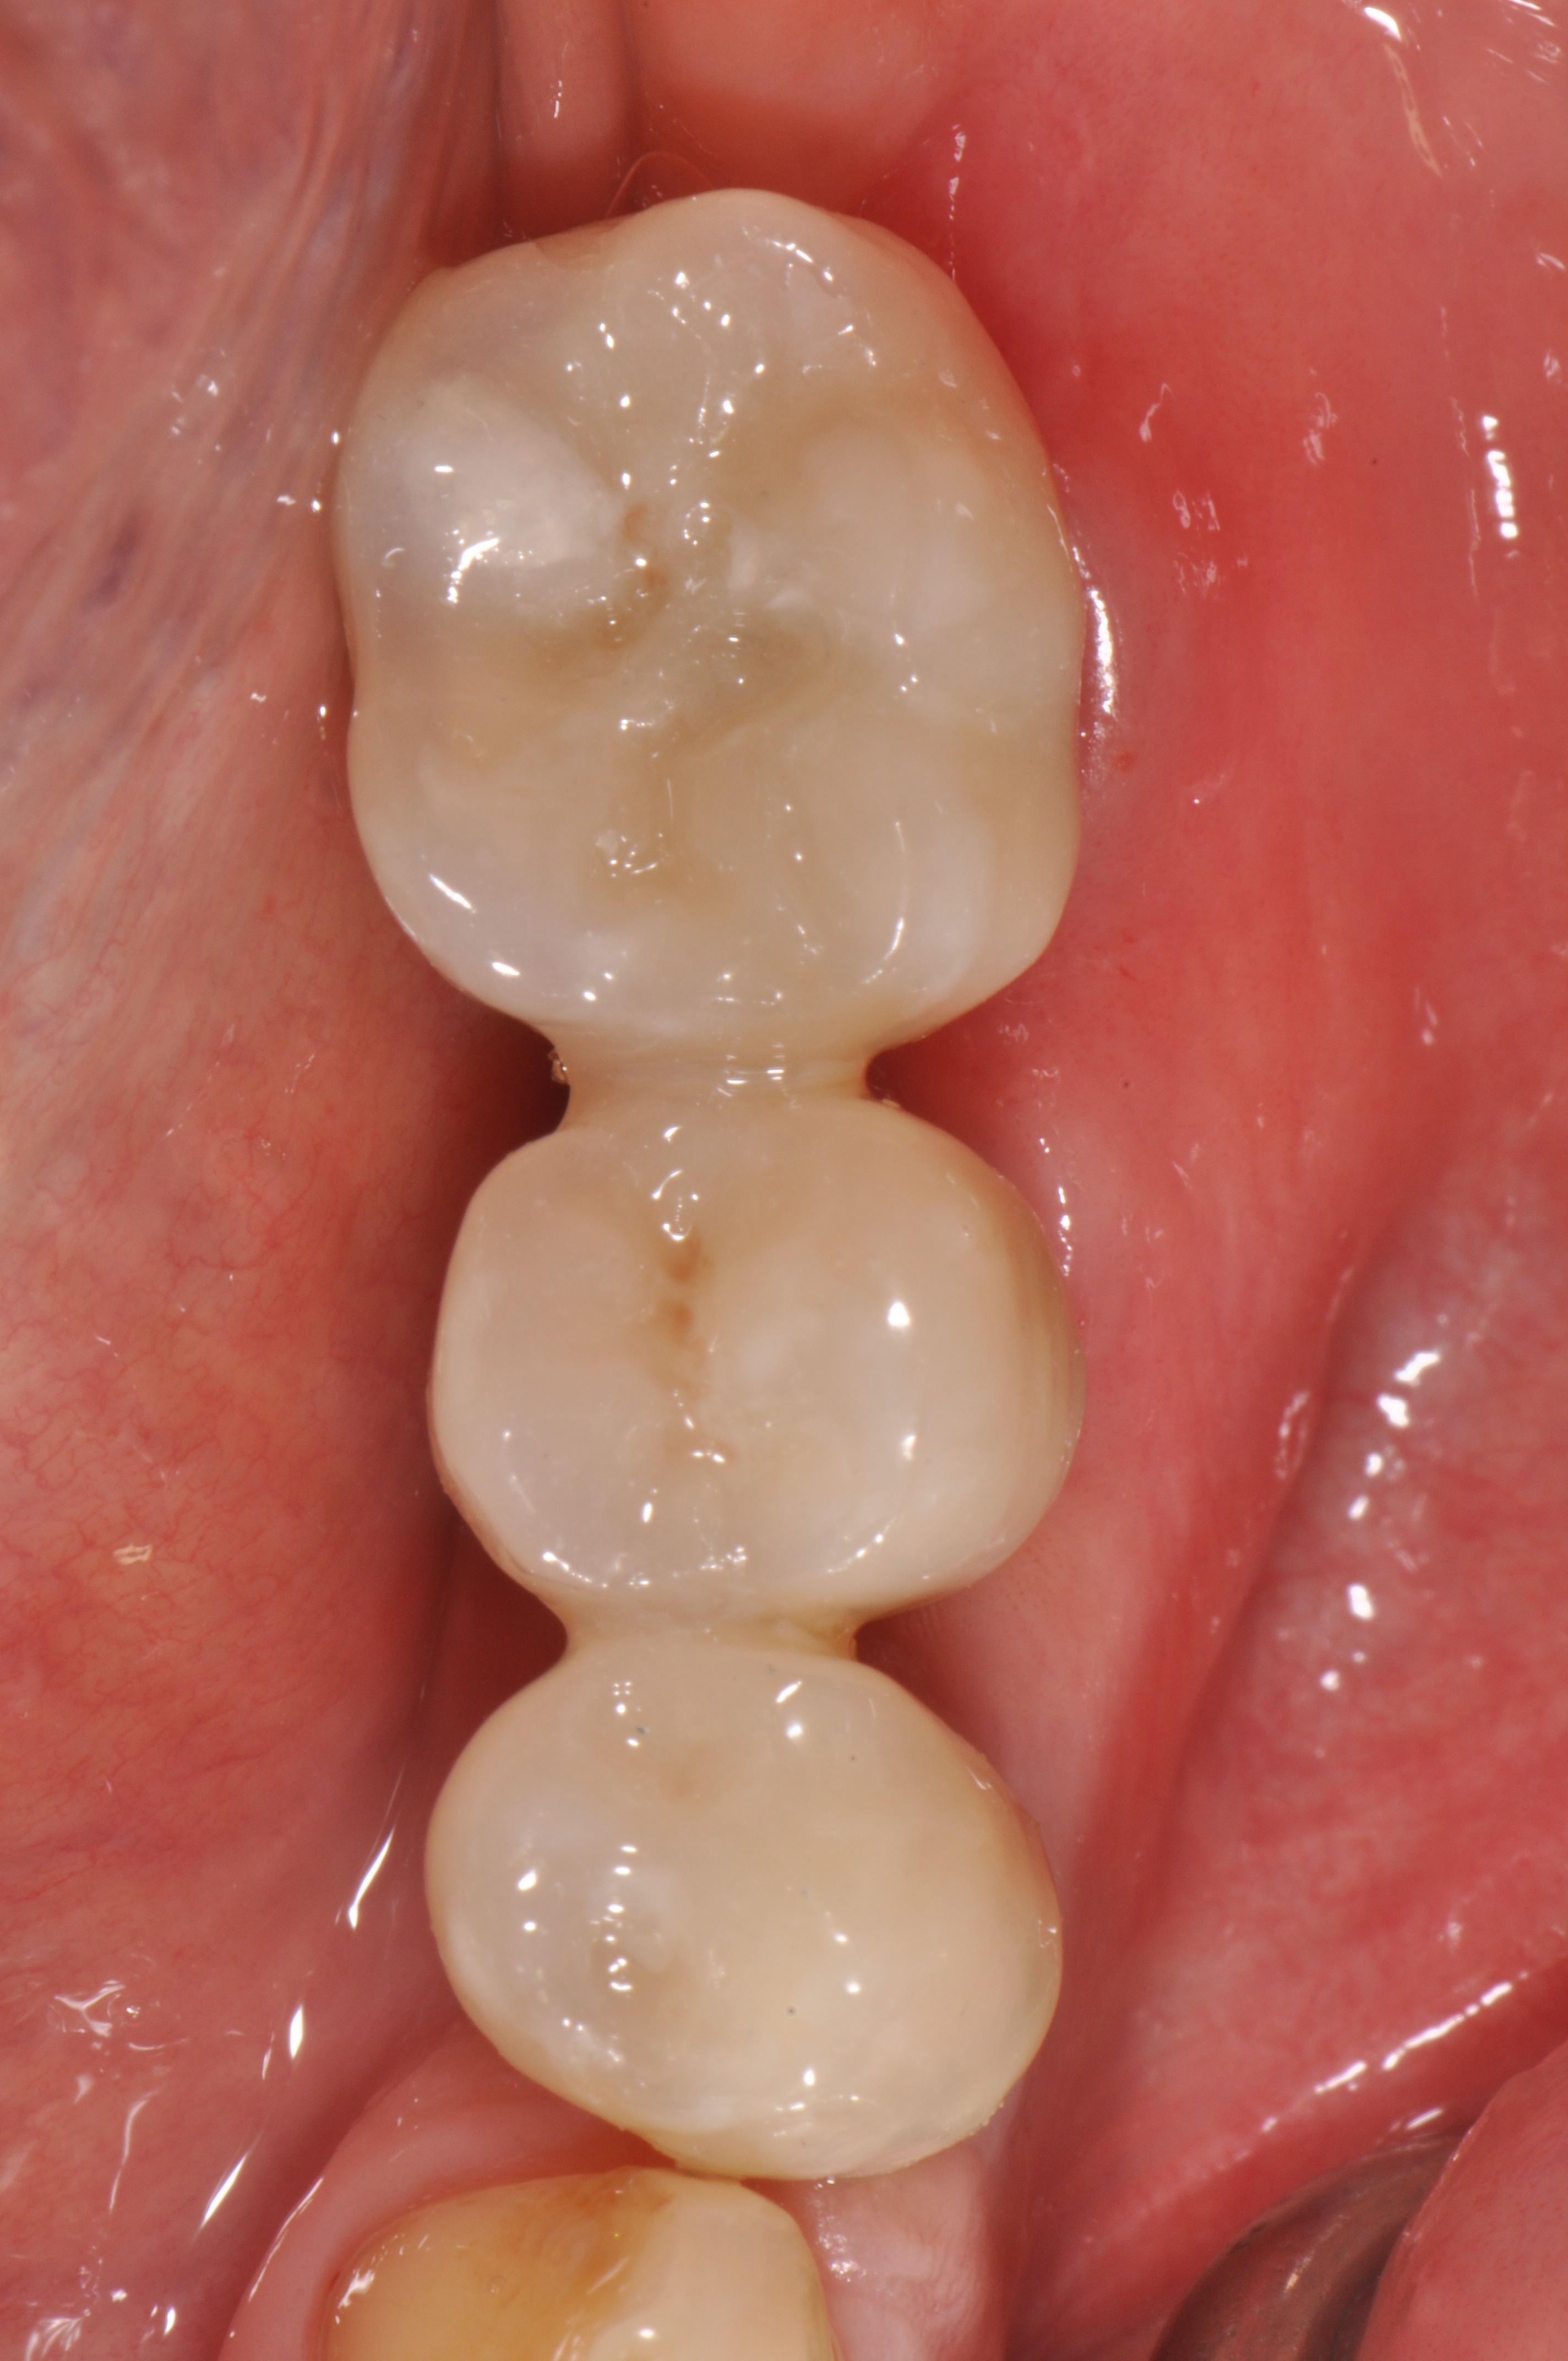

Replacement of a fixed partial denture with three implants

A 52-year-old patient is a referral and has been wearing an immediate provisional partial denture after replacement of her worn and fractured fixed partial denture. As a definitive treatment solution, the patient desired "beautiful and long-lasting" implant-supported single crowns. Clinically the CT-scan revealed a very narrow bone crest ("knife-edge") in the 3rd quadrant. Implant placement has been planned with a simultaneous GBR procedure.